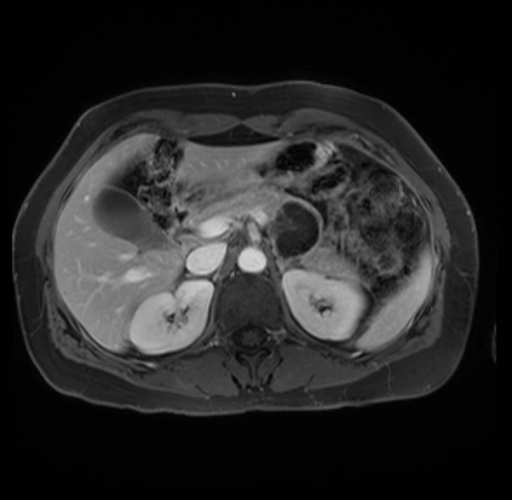

Imaging Analysis

Look through the patient's CT scan to identify any areas of concern for the necessary procedure.

Based on your CT findings, which issue(s) are present and would give reason for "planned slowing down moment(s)" in this case?